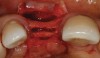

A 45-year-old woman presented with a narrow edentulous ridge in the maxilla (Figure 1). Following adequate anesthesia, a horizontal incision palatal to the crest and two vertical incisions were placed to outline the surgical field. A periodontal probe was used to measure the width of the alveolar crest at the most coronal dimension after a full-thickness flap was elevated (Figure 2). From the author’s experience, it was not necessary to maintain palatal bone-periosteum.

A long diamond bur was used to make a cut, which was 6-mm to 8-mm deep in the center of the alveolar ridge (Figure 3). The cut was made at least 1 mm away from the adjacent teeth in order to prevent any damage to them. A 4-mm wide bone-spreading chisel was used to mobilize and displace the buccal plate facially (Figure 4) so that a small, tapered osteotome for expansion could be used for implant site preparations. A 2-mm round bur was used to mark the implant location, and a 2-mm twist drill was used to guide the expansion with osteotomes.